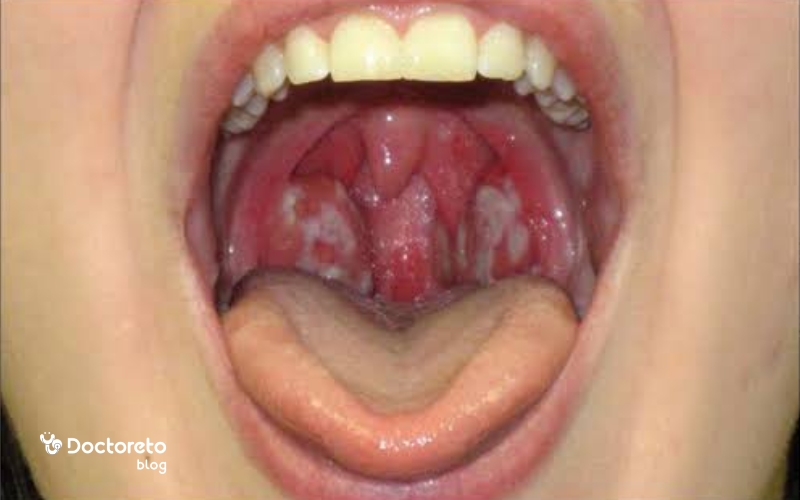

- گاهی لکههای سفید یا زرد روی لوزهها (در عفونت باکتریایی)

- التهاب گلو باکتریایی: اغلب توسط باکتری استرپتوکوک گروه A ایجاد میشود و با تب و لکههای سفید روی گلو همراه است.

| پلاک سفید روی لوزهها | ندارد یا کم | دارد (پلاک سفید یا زرد) | ندارد |